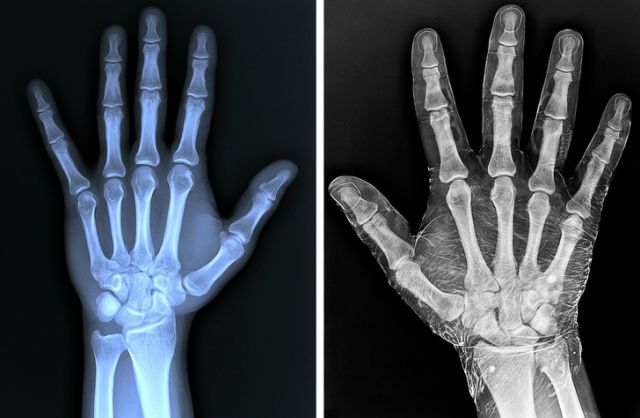

左侧为普通拍摄,右侧为涂抹了碘伏后再进行拍摄。

三岁孩子和六岁孩子的手,随着年龄的增长,骨骼之间的缝隙也越来越紧。